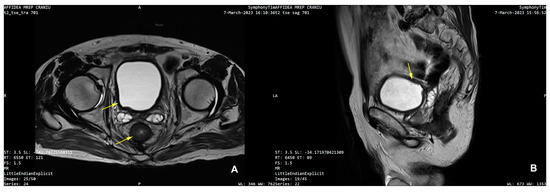

3. Detailed Case Description

| 25 | Present Case (2025) | 64/M | UCC G3/conventional and signet ring cell | GATA3, CK 20/CK5/6, P63, CDX | colonoscopy, rectal EUS TCB | rectal tenesmus, transit disorders (constipation/small volume diarrhea), moderate dysuria | DISTAL MEDIUM R |

| 25. | Present Case (2025) | 64/M | 0 | NO | Colostomy, NEOADJ CHT GC, RT | 15 M/D | T2N0M0 |